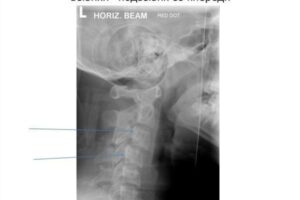

Лечение и диагностика подвывиха шейного позвонка

Подвывих шейки матки — это аномальное смещение соседних позвонков. Это явление встречается как у взрослых, так и у детей. Важное условие при подвывихе — обращение за квалифицированной медицинской помощью. Самолечение может только усугубить ситуацию. Причины патологии Причины подвывиха шейных позвонков могут быть разными. К ним относятся: Резкий поворот головы. Этот фактор особенно характерен для детей …